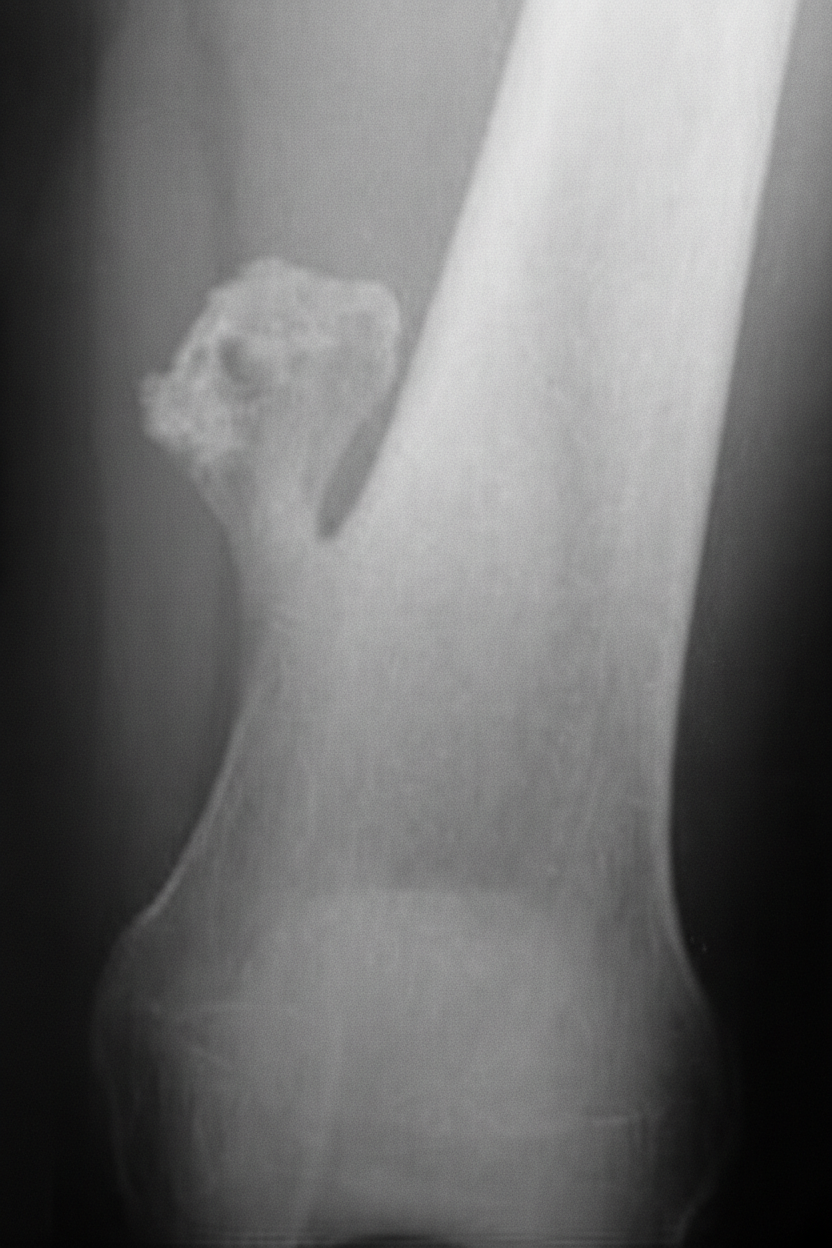

A 12-year-old Caucasian male presents with his mother to the pediatrician’s office complaining of right thigh pain. He reports that he has noticed slowly progressive pain and swelling over the distal aspect of his right thigh over the past two months. He denies any recent trauma to the area and his temperature is 100.9°F (38.3°C). On exam, there is swelling and tenderness overlying the distal right femoral diaphysis. Laboratory evaluation is notable for an elevated white blood cell (WBC) count and elevated erythrocyte sedimentation rate (ESR). A radiograph of the patient’s right leg is shown. Biopsy of the lesion demonstrates sheets of monotonous small round blue cells with minimal cytoplasm. Which of the following genetic mutations is most likely associated with this patient’s condition?

Explanation: ***t(11;22)*** - The clinical presentation of a **12-year-old male** with progressive **thigh pain and swelling**, fever, elevated WBC and ESR, a radiograph showing a bone lesion [1], and a biopsy revealing **small round blue cells with minimal cytoplasm**, is highly suggestive of **Ewing sarcoma** [2]. - **Ewing sarcoma** is characterized by the **t(11;22)(q24;q12) chromosomal translocation**, which fuses the *EWSR1* gene with the *FLI1* gene, leading to the formation of a chimeric transcription factor. *t(X;18)* - The **t(X;18) translocation** is the characteristic genetic abnormality of **synovial sarcoma**, another soft tissue malignancy. - While synovial sarcoma can also present in young patients, it typically affects older adolescents and young adults, and the histology differs from the small round blue cell pattern seen in Ewing sarcoma [2]. *RB1 inactivation* - **RB1 gene inactivation** is centrally involved in the pathogenesis of **retinoblastoma**, a childhood eye cancer. - It also plays a role in various other cancers, such as **osteosarcoma** [3] and small cell lung cancer, but its primary association is not with Ewing sarcoma. *TP53 inactivation* - **TP53 gene inactivation** is a common event in a wide range of human cancers, as *TP53* is a critical **tumor suppressor gene**. - While *TP53* mutations can be found in some sarcomas, it is not the defining or most likely specific genetic mutation for **Ewing sarcoma**. *t(8;14)* - The **t(8;14)(q24;q32) chromosomal translocation** is the characteristic genetic abnormality found in **Burkitt lymphoma**. - This translocation leads to the **c-MYC proto-oncogene** being placed near the immunoglobulin heavy chain locus, promoting its overexpression, which is unrelated to Ewing sarcoma. **References:** [1] Cross SS. Underwood's Pathology: A Clinical Approach. 6th ed. Common Clinical Problems From Osteoarticular And Connective Tissue Disease, pp. 671-672. [2] Kumar V, Abbas AK, et al.. Robbins and Cotran Pathologic Basis of Disease. 9th ed. Bones, Joints, and Soft Tissue Tumors, pp. 1204-1205. [3] Kumar V, Abbas AK, et al.. Robbins and Cotran Pathologic Basis of Disease. 9th ed. Bones, Joints, and Soft Tissue Tumors, pp. 1200-1202.